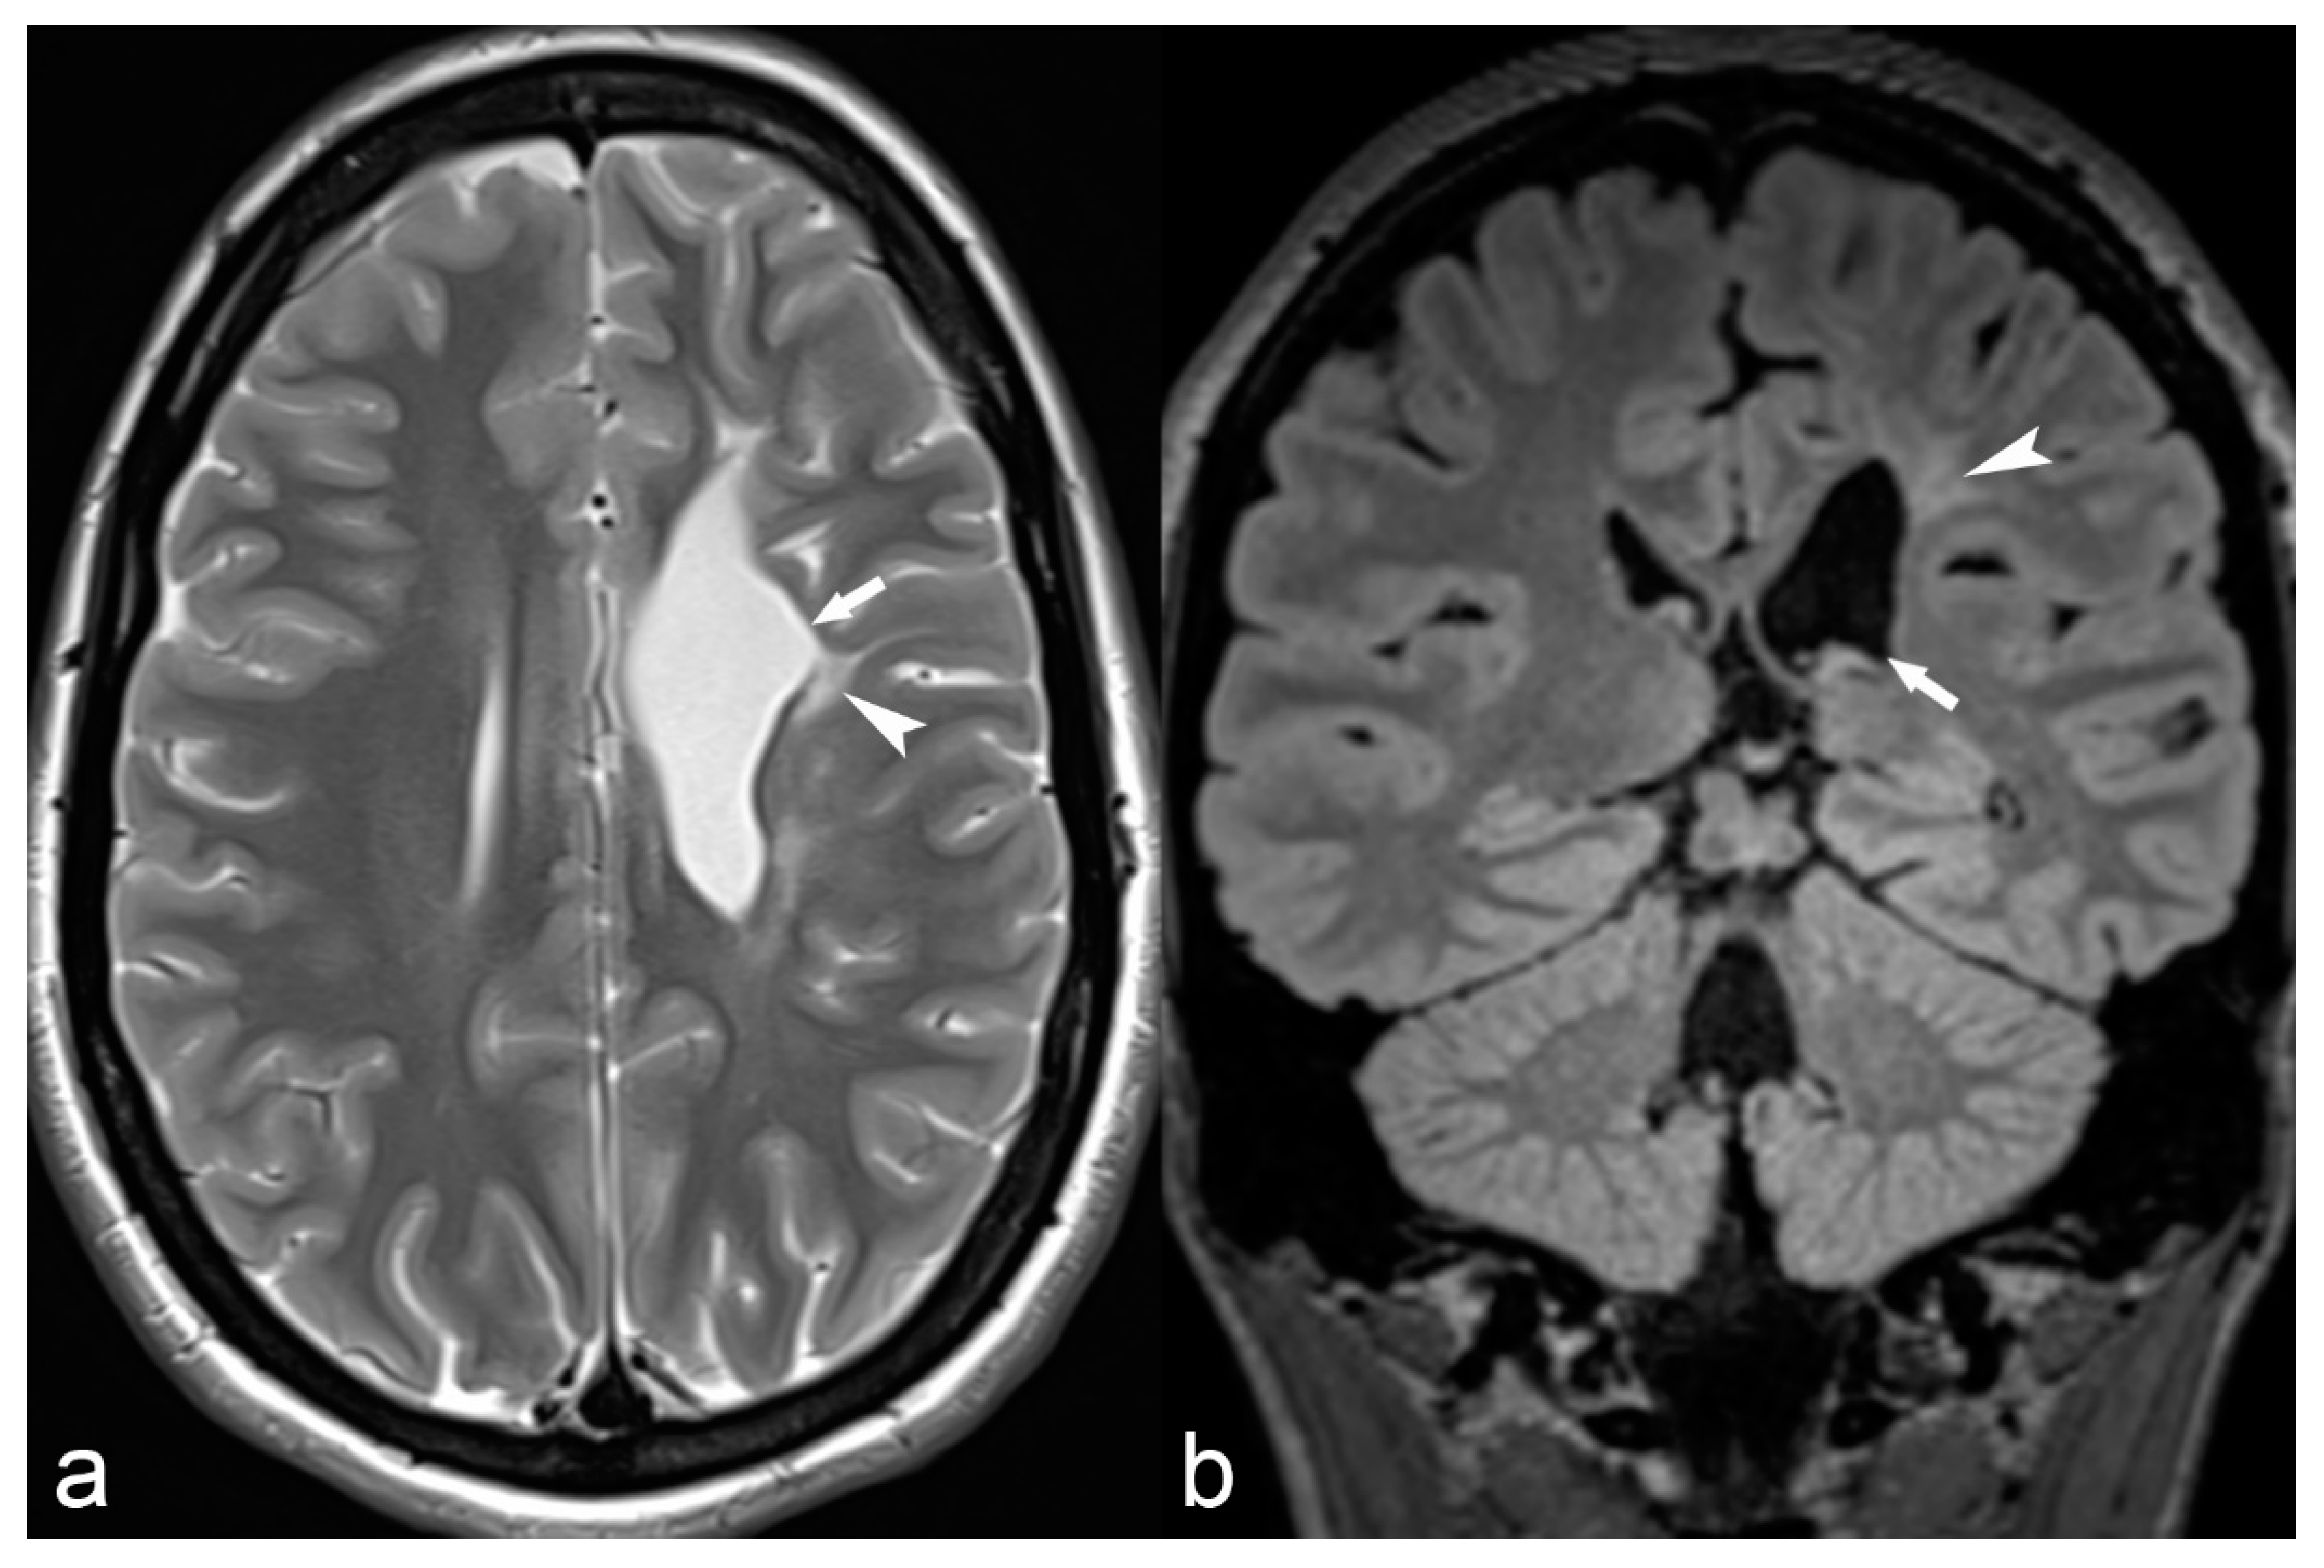

Meningoencephaloceles are probably an underreported cause of epilepsy, most commonly located in the middle cranial fossa. Smaller or larger bony defects of the greater wing of the sphenoid can result in encephaloceles, which cause irritation of the cortex and epilepsy, and their depiction sometimes requires a combination of thin-slice CT in the bony window and high-resolution coronal T2 MRI images (Figure 14).

Figure 14.

68-year-old woman with left temporal meningoencephalocele. Axial 3D high-ponderated T2 sequence (a) shows herniation of abnormal brain parenchyma, meninges and cerebrospinal fluid (arrow) into a defect of the greater wing of the sphenoid bone, best seen on CT in the bone window (arrowhead in (b)). This is further illustrated by a 3D cinematic rendering of the 3D T2 acquisition with a left posterior-anterior oblique vantage point (c), which demonstrates the full caudal extent of the meningoencephalocele within the sphenoid bone (arrow).